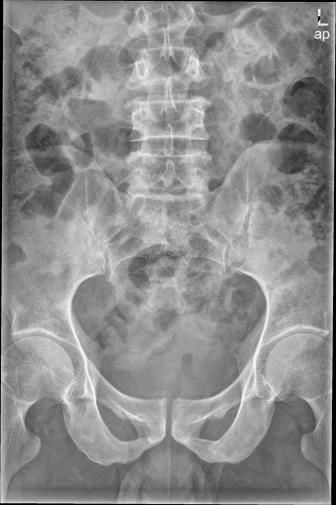

ABC (Aneurysmal bone cyst)动脉瘤样骨囊肿

好发于10~30y,病变起源于附件,向椎体后方发展,或病变局限于椎体一侧

膨胀性骨质破坏,有钙化及分隔;可跨过椎间隙累及相邻椎体或肋骨

MRI:液液分层(典型表现)

Case10:F,10y;腰痛1月加重2天,无肢体麻木、乏力,无二便障碍 。

文章插图